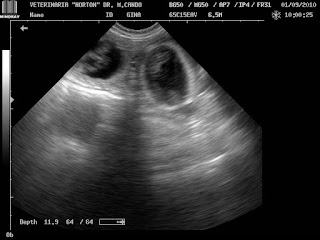

G-H-I. COMPROBACIÓN DE LA RUPTURA DEL LCA POR ARTROTOMÍA DE LA ARTICULACIÓN DE LA RODILLA